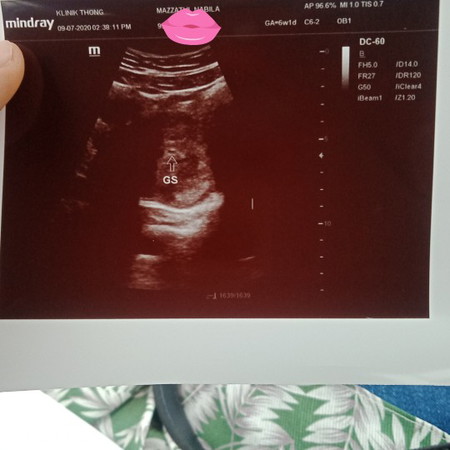

Ade sesape tahu knpe kandungan jadi mcm tuu? Sbb masa 4weeks scan doc ckp nmpk. Tdi pegi scan doc ckp kecik lagi n kemungkinan kandungan tk jadi 😭😭😭 test upt naik dble line. Ape patut saya buat? Boleh ke saya bukak buku pink kt kk?

kecik lg sy 4w tak nampak apa, then doc sruh mai lg dua minggu scan nmpk kantung jaa keep positive pastu p 9w dh nampak janinn p 13w nampak dia dh pusing2

Saya hr tu..5 weeks scan ada kantung je..8 weeks pun x nampak lg baby..10 weeks baru nampak baby & heart beat dia..